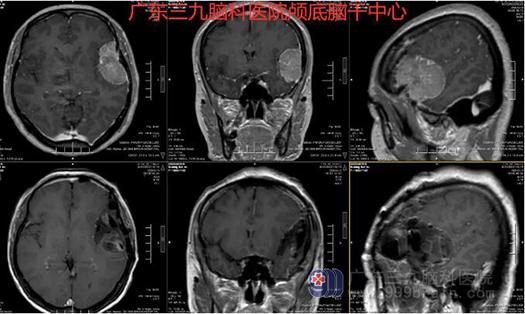

图3:术前术后MR示左侧额颞部颅骨内板下占位性病变已切除